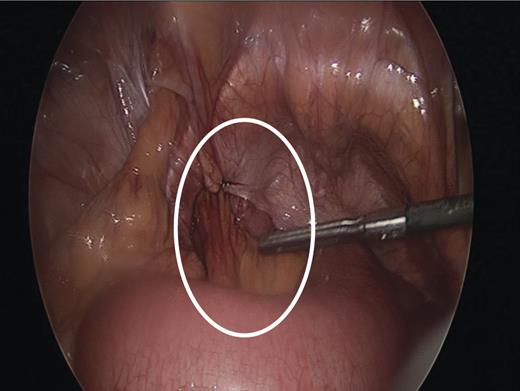

Under general anaesthetic, the optical technique for access was utilized at the umbilicus with a 5 mm port. Two further working ports, a 5 and 10 mm, were placed in the right lower quadrant and right hypochondrium, under direct vision. Findings included visualization of small bowel dilatation down to small bowel in a left obturator hernia with an incidental left femoral hernia containing omentum (Fig. 2). The incarcerated small bowel was reduced using a pair of non-traumatic forceps and deemed viable. The omentum was reduced from the femoral hernia.

Intraoperative image showing left sided obturator hernia within white outline and incidental femoral hernia at 11’o clock position.